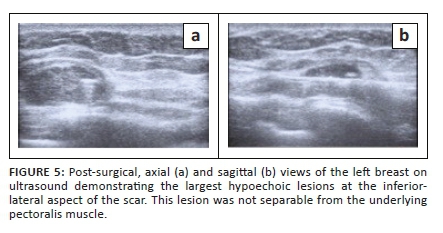

The patient then defaulted on her follow-up appointments including an appointment for a staging CT scan. Five months after the mastectomy, she was referred for a repeat mammogram and ultrasound for multiple large lesions at the left mastectomy site. The mammogram of the left scar demonstrated a 50 mm × 60 mm hyper-dense mass within the axillary tail as displayed in Figure 4. Ultrasound of the left mastectomy site demonstrated round hypoechoic lesions at the scar as demonstrated in Figures 5a and 5b. The largest measured 20 mm × 11 mm, situated at the inferior-lateral aspect of the scar and not separable from the underlying pectoralis muscle. Large axillary masses consisting of fluid with areas in keeping with soft tissue densities were demonstrated; the largest measured 56 mm × 38 mm. The lesion was classified as BI-RADS 4C. Ultrasound-guided core biopsy of the largest lesion demonstrated a poorly differentiated malignancy with OGCs - features in keeping with recurrence. The patient underwent a single cycle of radiotherapy and was then referred to oncology where she was treated with adriamycin and continues follow-up.